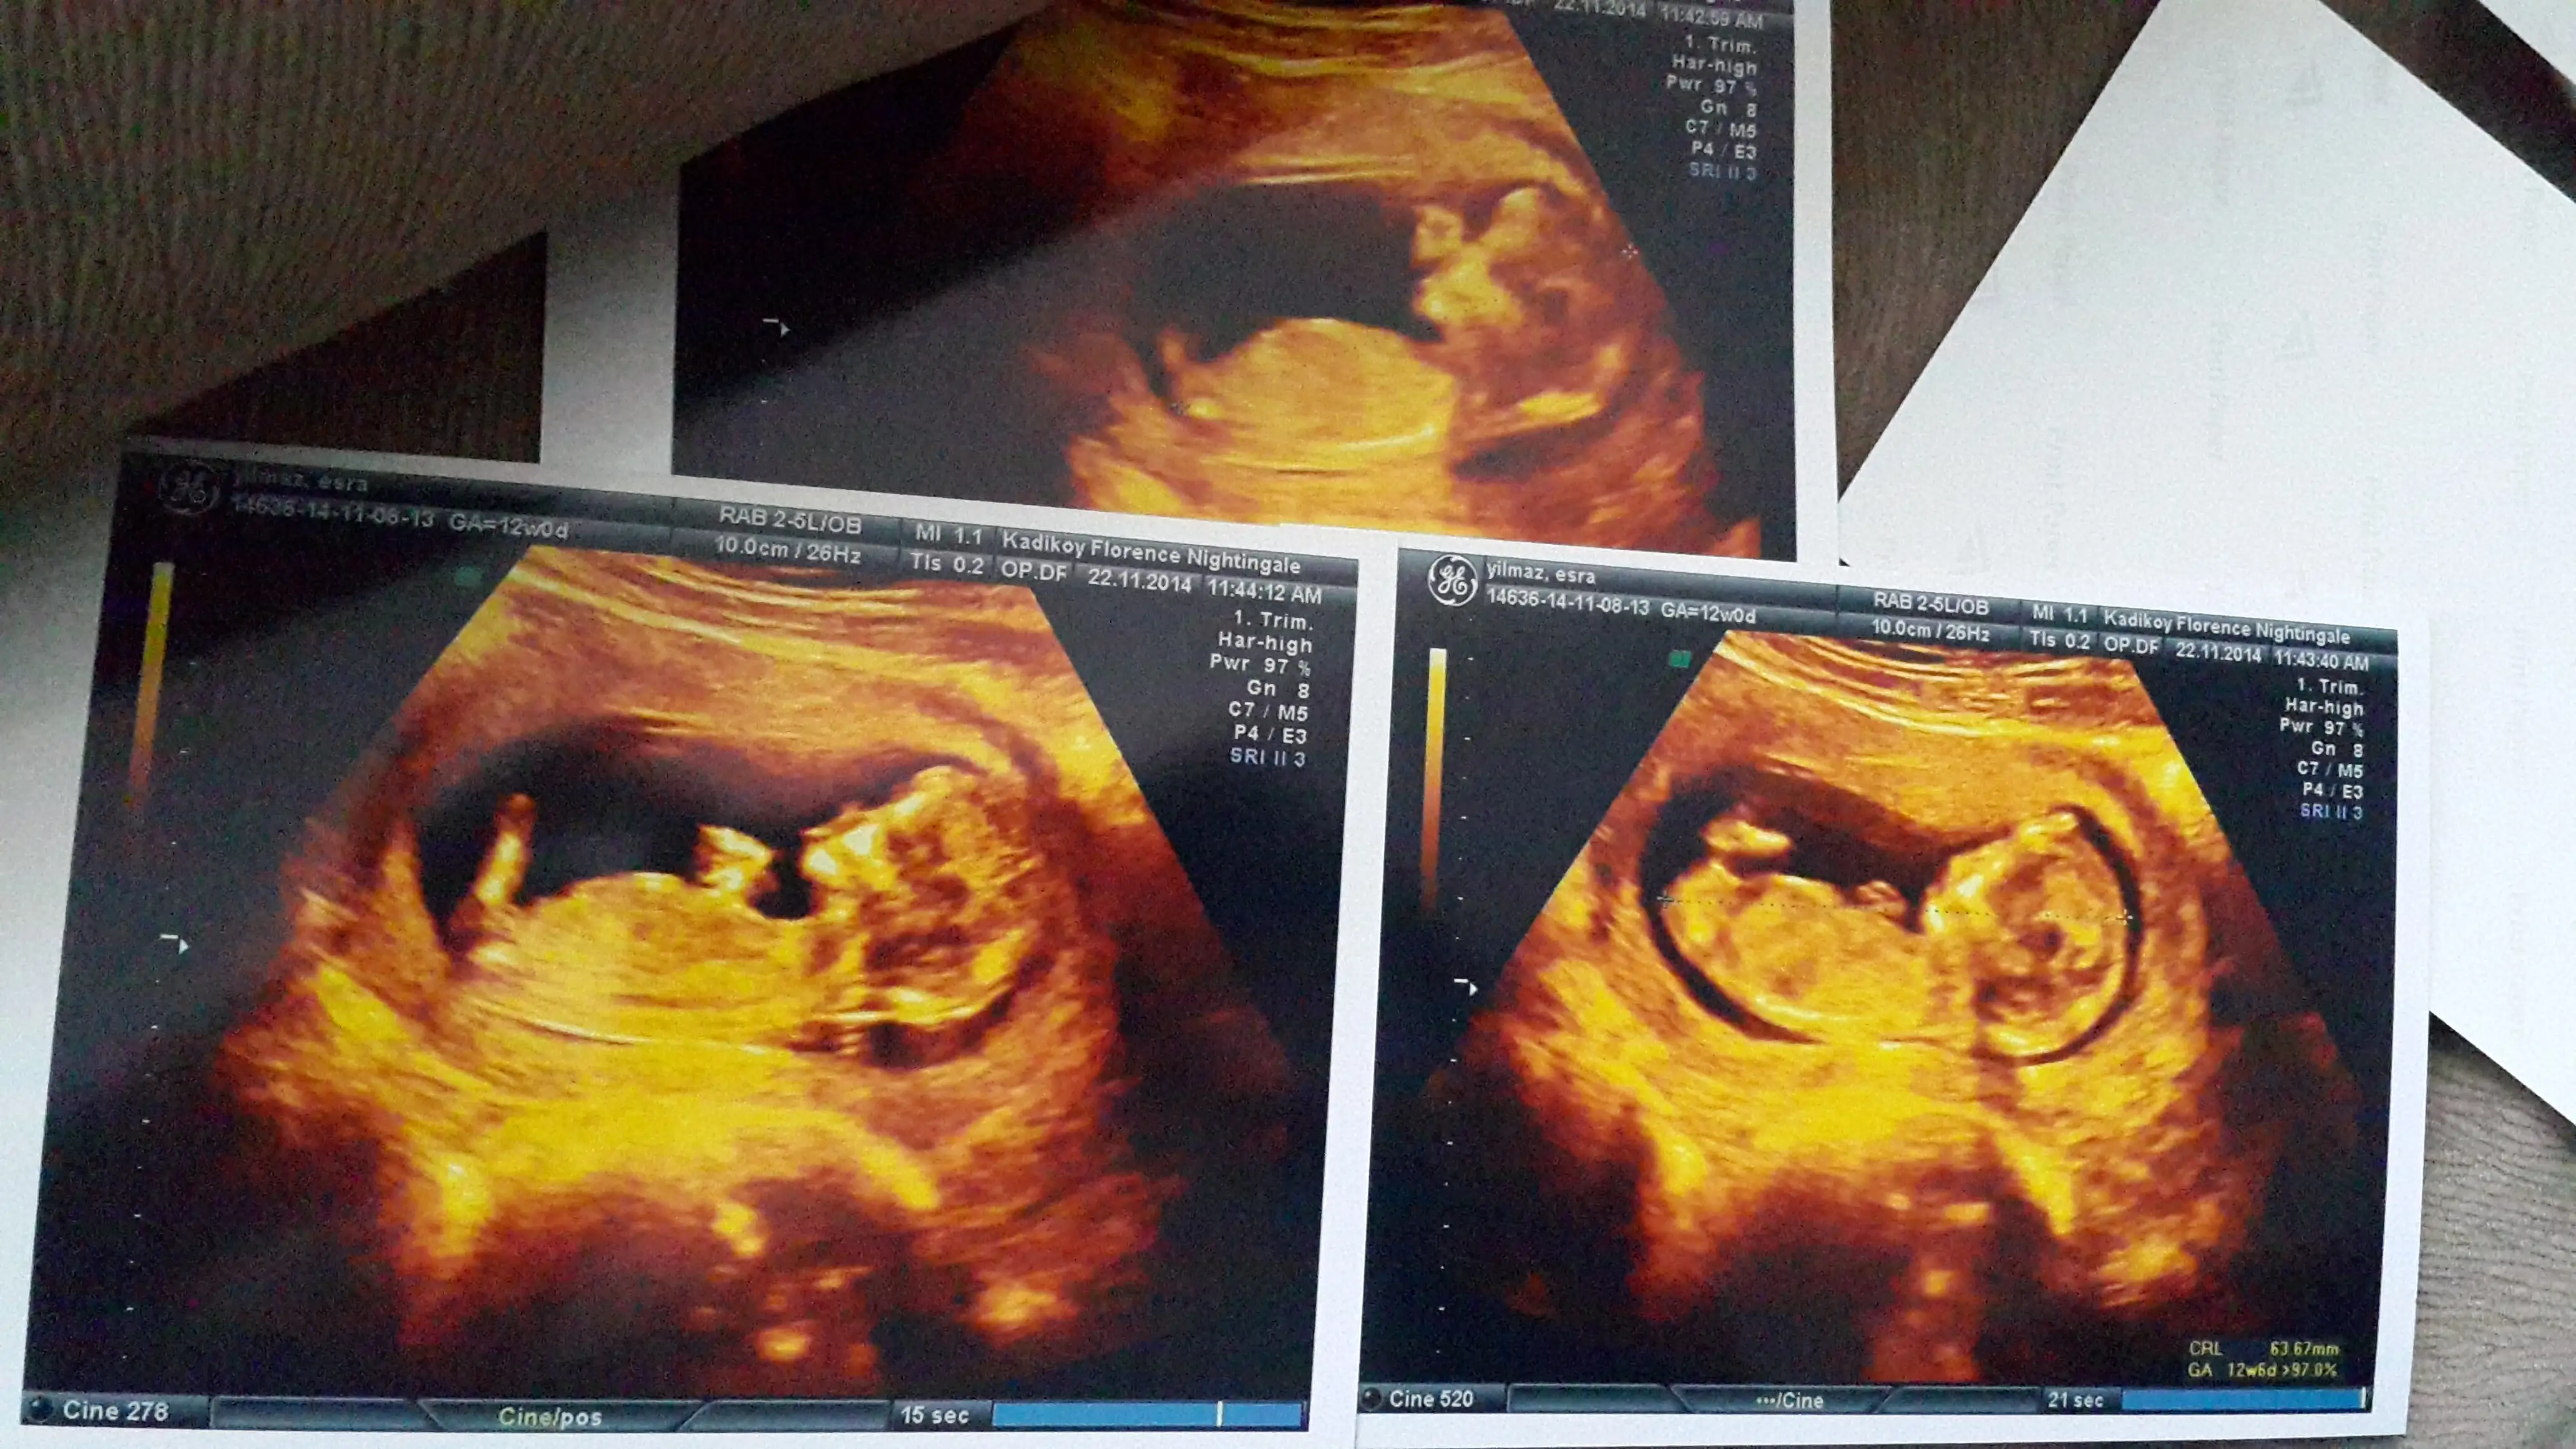

12+3 tûk burda :)

Simdiden kocaman tesekkurler

ilk resim 10 haftalık ikincisi 11+5 haftalık sizce cinsiyeti ne. ikincide sanki sırtı dönük:(

Bir de bu var ama bacaklar yukarida degil. Tam donucekmis bebisim :)